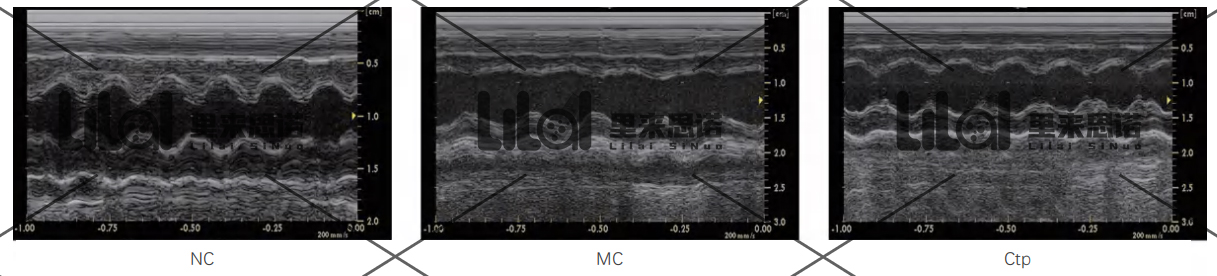

SPF級(jí)SD大鼠180~220 g,雄性。將大鼠隨機(jī)分為空白對(duì)照組(NC)、模型組(MC)、陽性對(duì)照組(Captopril, Ctp)。

心功能檢測(cè):實(shí)驗(yàn)結(jié)束后進(jìn)行心臟超聲,檢測(cè)各組大鼠的心功能。結(jié)果發(fā)現(xiàn):與NC組相比,MC組大鼠左室射血分?jǐn)?shù)(LVEF)和左室短軸縮短率

(LVFS)顯著降低;而Ctp能顯著提高心衰大鼠LVEF和LVFS,改善心衰大鼠心功能(p<0.01)。